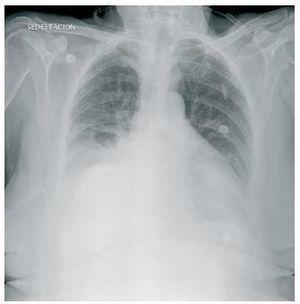

Se trata de una mujer de 76 años, con insuficiencia renal crónica estadio 5 por nefropatía intersticial, que realiza diálisis peritoneal continua ambulatoria desde hace 3 años. Su pauta habitual es tres recambios diarios de 2.000 ml. En este tiempo no ha tenido peritonitis y no ha sido sometida a ninguna intervención quirúrgica. En una revisión rutinaria se detecta una pequeña hernia umbilical, no incarcerada, y una hernia abdominal, de unos 6 cm de diámetro, en línea paramedial izquierda, que se confirma mediante ecografía y TC. La dinámica de la diálisis peritoneal no se ve afectada por estas alteraciones anatómicas, por lo que se decide, tras valoración quirúrgica, mantener una actitud conservadora, modificando la pauta de diálisis a cuatro recambios diarios de 1.500 ml. A los 6 meses acude al hospital por líquido turbio, febrícula y leve dolor abdominal, de 5 horas de evolución. En días previos había presentado un cuadro diarreico leve. El recuento celular del efluente peritoneal muestra 4.570 células/ml (98% PMN). Con el diagnóstico de peritonitis bacteriana en diálisis peritoneal se decide su ingreso hospitalario y se inicia antibioterapia intraperitoneal según protocolo de nuestro centro: vancomicina, ampicilina y tobramicina. Al día siguiente mantiene líquido turbio, con recuento celular de 9.850 célulasl/ml (94% PMN); el balance de DP muestra una ganancia de 1.200 ml y persiste un leve dolor abdominal. A las 36 horas del ingreso avisan por disnea súbita. La paciente presenta mal estado general, está pálida, sudorosa, taquipneica y con trabajo respiratorio. La saturación de oxígeno es del 90%. En la auscultación pulmonar se aprecia una disminución del murmullo vesicular en hemitórax derecho. En la radiografía de tórax se observa un derrame pleural derecho moderado (figura 1). Se realiza un recambio hipertónico de corta duración, sin mejoría. A la vista del cuadro de dificultad respiratoria paroxística y la imagen radiológica indicativa, se recurre a una toracocentesis evacuadora, que drena 2.000 ml. El líquido pleural presenta una concentración de glucosa de 269 mg/dl, muy superior a la plasmática (110 mg/dl), lo cual confirma el diagnóstico de hidrotórax. Tras el drenaje pleural, la clínica mejora significativamente. Se suspende la diálisis peritoneal y, al recibir el resultado del cultivo del líquido peritoneal, que es positivo para Bacteroides fragilis, se inicia antibioterapia intravenosa con meropenem y metronidazol. Mediante TC abdominal se descarta la existencia de perforación y resto de patología intraabdominal. Tras 2 semanas de tratamiento, es dada de alta y permanece actualmente en hemodiálisis periódica.

Figura 1. Hidrotórax.